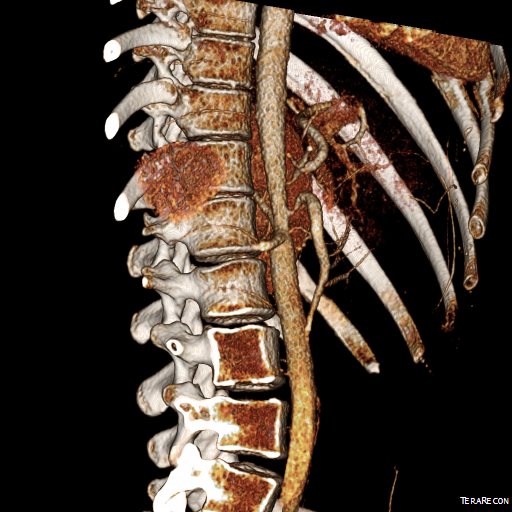

Examination was remarkable for a well nourished young woman in distress with epigastric tenderness. Inflammatory markers were normal and she was on methotrexate and tocilizumab. CTA (above) and duplex showed severe stenoses affecting the origins of the celiac axis and superior mesenteric artery. A composite of the centerlines through these showed the arteries to be critically narrowed at their origins (below), along with a mild to moderate stenosis of the aorta (above). No active inflammation could be seen.

precenterlineCA and SMA.png

The anterior view of the 3DVR images of her CT showed an absence of collateralization via the inferior mesenteric artery and Arc of Riolan.

preCTA_3.jpg